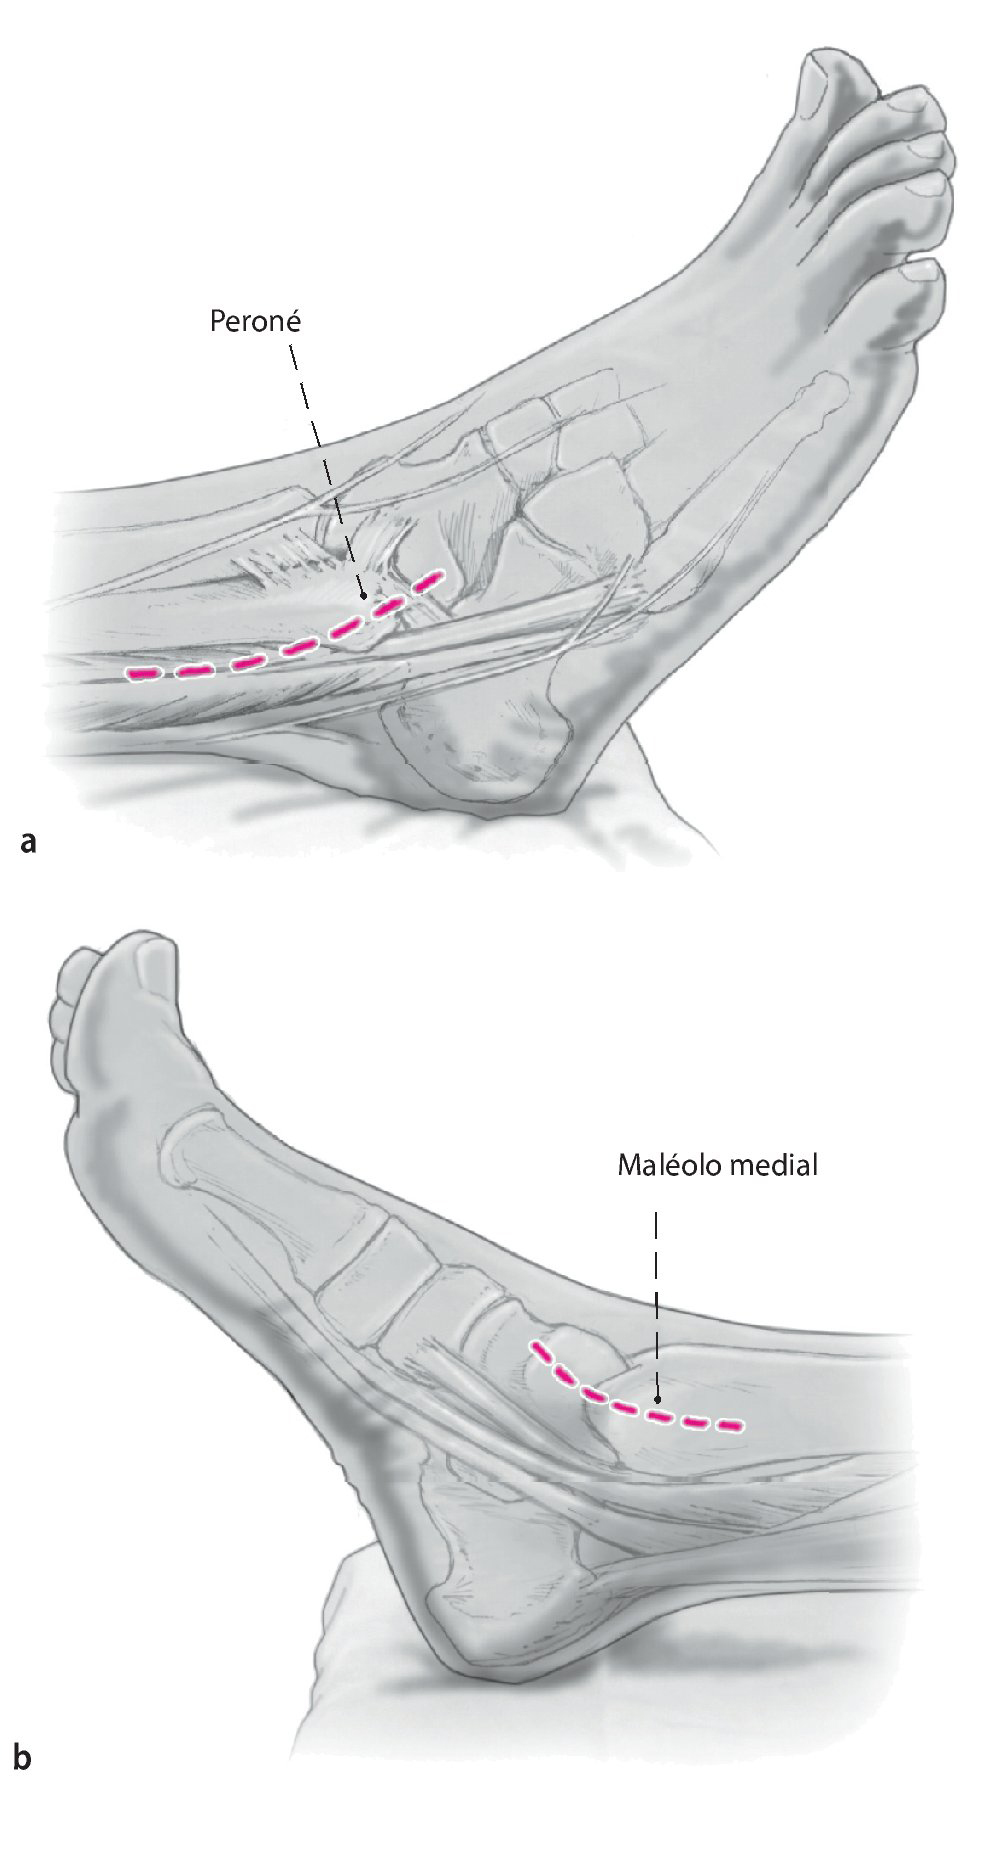

Fig. 1 Incisión lateral (a) y medial (b) . Ambas de 6-8 cm de longitud y el uso del maléolo lateral y medial como puntos de referencia.